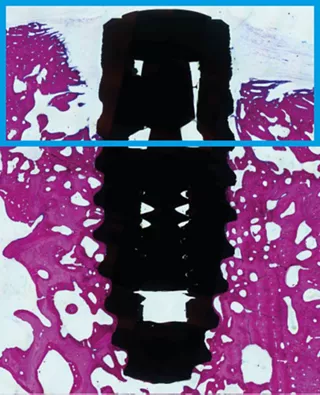

Bone defects can greatly compromise the predictability of osseointegration. In a recent preclinical study22, SLActive® showed significantly higher formation of new bone aggregate within eight weeks compared to the standard Straumann® SLA® hydrophobic surface.

Bone aggregate formation at 8 weeks.22

22 El Chaar E, Zhang L, Zhou Y, et al. Osseointegration of Superhydrophilic Implants Placed in Defect Grafted Bones. International Journal of Oral & Maxillofacial Implants . Mar/Apr2019, Vol. 34 Issue 2, p443-450